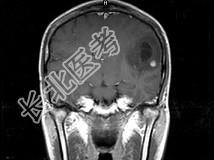

- 单项选择题女,33岁, 3个月前有右上肢及右颜面部麻木,伴耳鸣及头昏, 根据所提供图像,最可能的诊断是 ( )

A、脑脓肿

B、星形细胞瘤

C、脑结核

D、脑转移瘤

E、脑血吸虫病